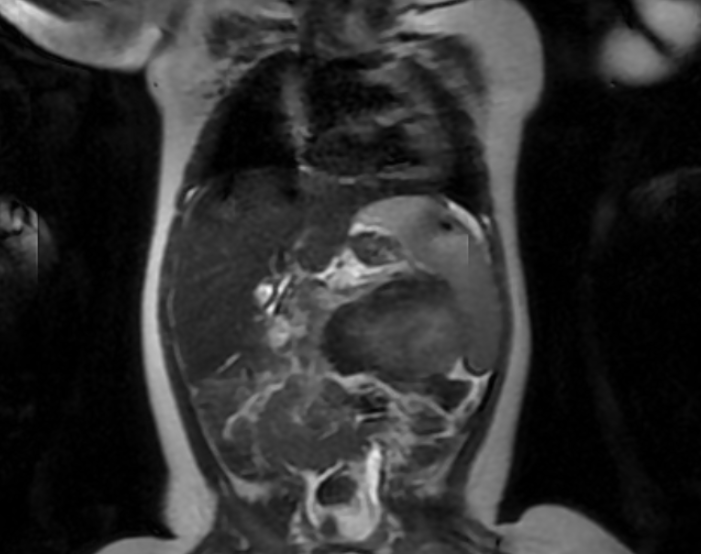

面对以“重度血小板减少、消耗性凝血病、腹部巨大包块”为特征的重症婴儿,诊断是首要挑战。在排除常见血液病及感染后,超声、核磁共振等影像学检查提示胰腺体尾部-脾门区占位。然而,儿童血液肿瘤科团队敏锐地抓住“婴儿期、急性病程、血小板减少伴消耗性凝血病”这一关键线索,高度怀疑患儿可能为罕见的“卡波西样血管内皮瘤合并卡梅现象”。